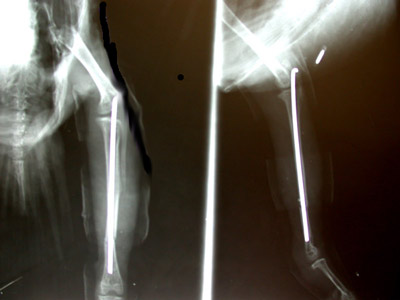

Versorgung eines Splitterbruches der Ferse einer Katze mit einem “Fixateur externe”. Der Knochen wurde offen wieder zusammengesetzt (reponiert) . Nachdem die Konstruktion aber nicht belastungsstabil sein konnte, wurden Drähte durchgebohrt.

Die Drähte werden durch eine aussenliegende Kunstoffbrücke zusammengehalten und der Bruch kann gut abheilen.